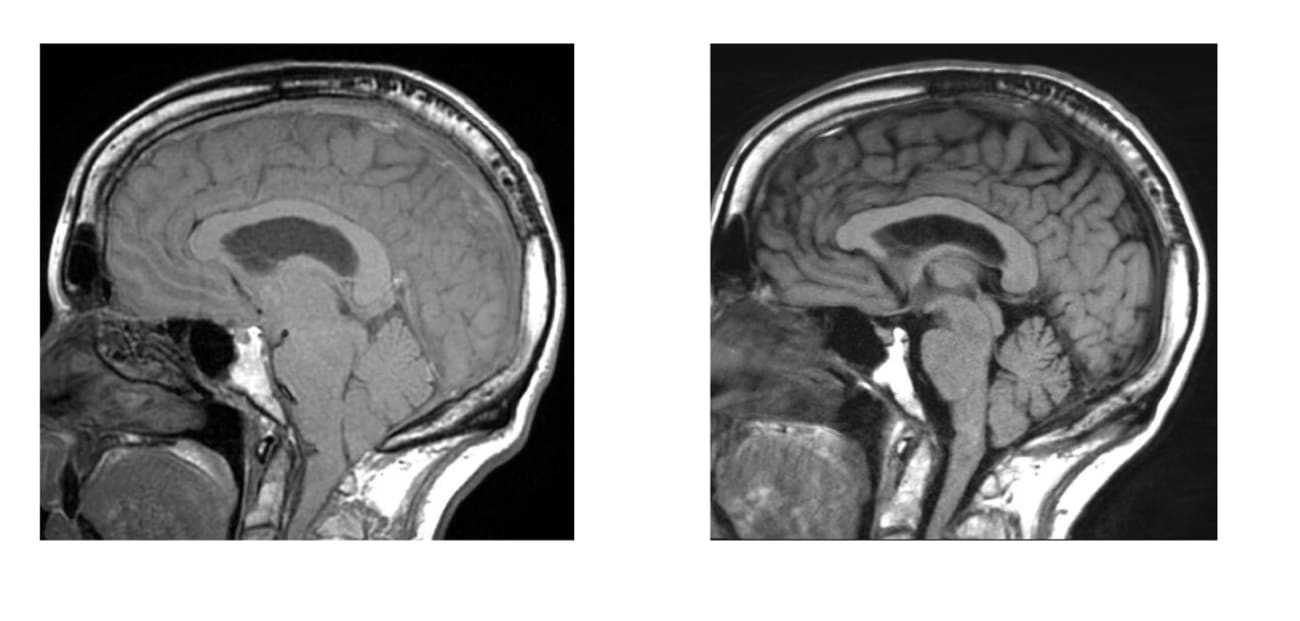

On the Left: An image of brain sagging. On the right: Post-op resolution of brain sagging

Cerebrospinal fluid (CSF) circulates in and around the brain and spinal cord to help cushion them from injury. When this fluid leaks into the body, the brain can sag, causing dementia symptoms. Schievink said many patients with brain sagging—which can be detected through MRI—go undiagnosed, and he advises clinicians to take a second look at patients with telltale symptoms.